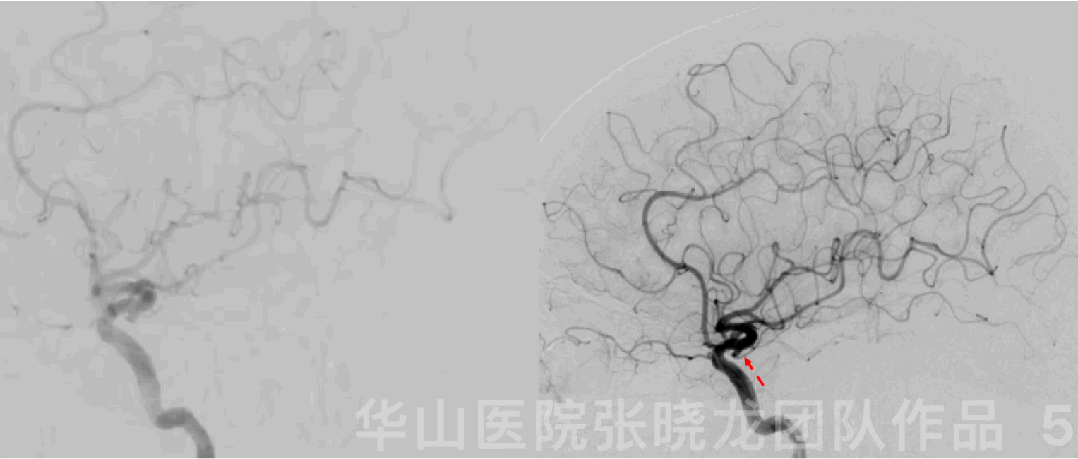

Figure 5 GIF. A left posterior communicating artery infundibulum was identified by angiograms.

图 5 GIF. DSA证实左侧后交通圆锥。